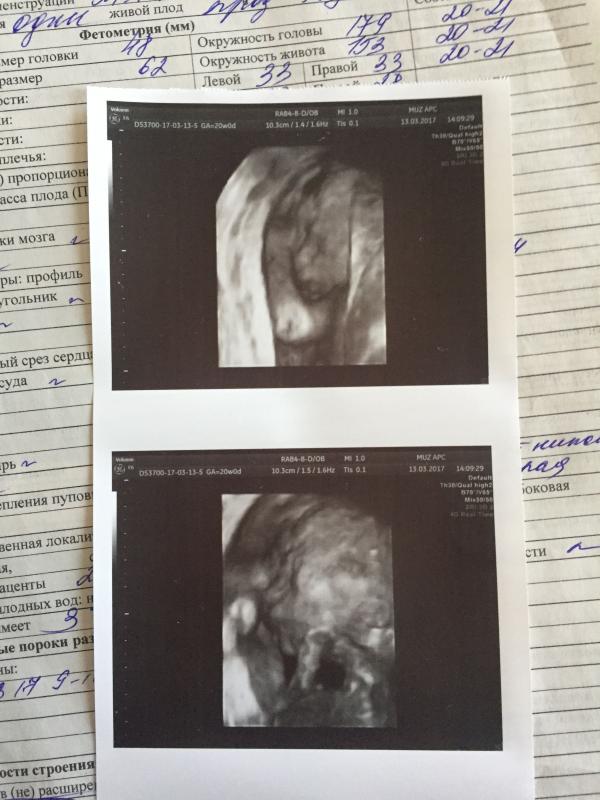

Ура 🎉 сегодня был 2 скрининг, малыш здоровый патологий не обнаружено 👼🏼 и сказали что будет мальчик 👶🏼 хотя все до этого говорили что будет девочка, даже врач 👨⚕️ когда живот замеряла говорила, что девочка🤷🏽♀️ но я очень рада что угодила отцу, очень хотел мальчика 🤰🏼правда фото сделано не понятно, на первом скрининге было лучше было вино малыша, а здесь ни чего не понятно 🤔 и ещё в заключении написано краевое прикрепление пуповины, кто с этим сталкивался? Расскажите пожалуйста 🙏🏼🙏🏼🙏🏼 очень переживаю😬